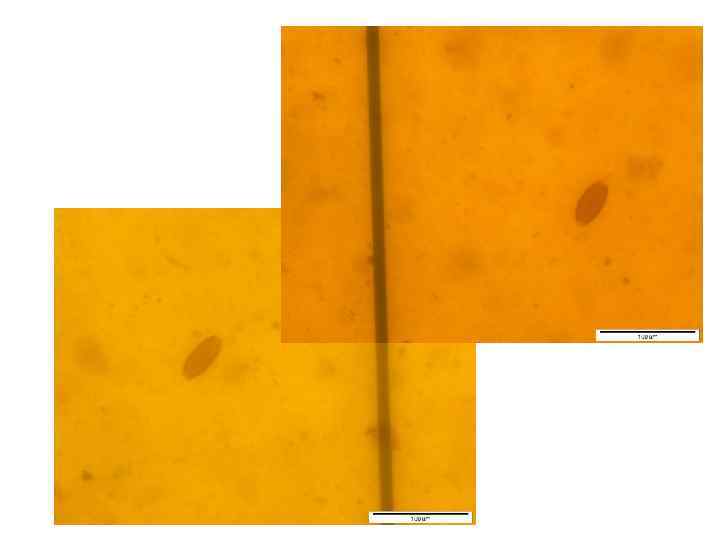

Вылупление зародышей нематоды из яиц in vitro

Тест развития личинок

C 21 dpi

C 21 dpi

C 35 dpi

Mo 14 dpi

Mo 14 dpi

34

© И. Г. Бондаренко, 2011